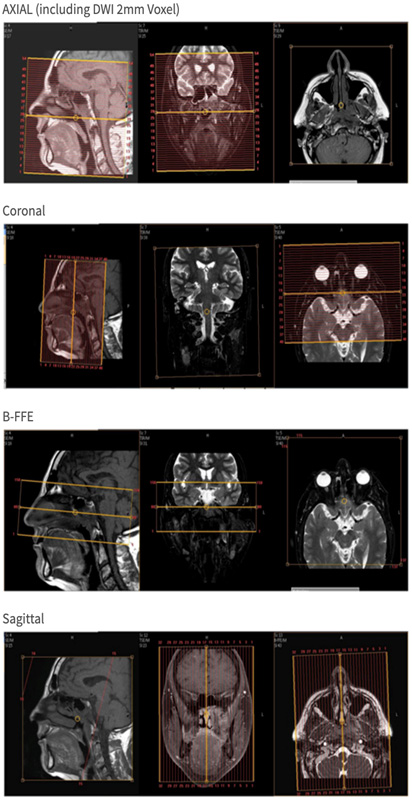

Sagittal: ear-to-ear, top of frontal sinus to hyoid bone and all of mandible, centered on posterior nasal cavity with FOV of about 180 x 180. Okay to exclude posterior neck/brain and superior brain.

Coronal: Tip of nose to 4th ventricle, top of frontal sinus to hyoid bone and all of mandible. FOV about 180 FH and 150 LR.

Axial: Top of frontal sinus to hyoid bone and all of mandible. Centered on posterior nasal cavity with FOV of about 180 AP x 170 LR. Okay to exclude posterior part of brain and posterior neck.

| AXIAL | T2 | BFFE | 1 | -0.5 | no | 18 | COR, SAG | 75 mm FH coverage centered on pons |